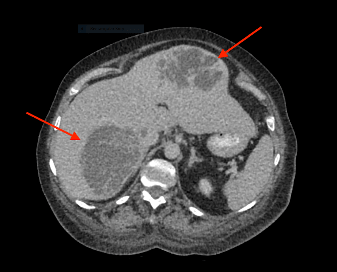

Patient was initially admitted under the medical team for management of likely haematological malignancy with symptomatic anaemia. On further investigation, CT abdomen demonstrated multicystic and solid hepatic masses suggestive of metastasis, but no primary malignancy detected (See figure 1). Findings were further confirmed with ultrasound liver.

Figure 1 (a, b, c): CT Abdomen showed multicystic and solid hepatic masses. Differential diagnosis includes hydatid cyst, metastasis or abscess.